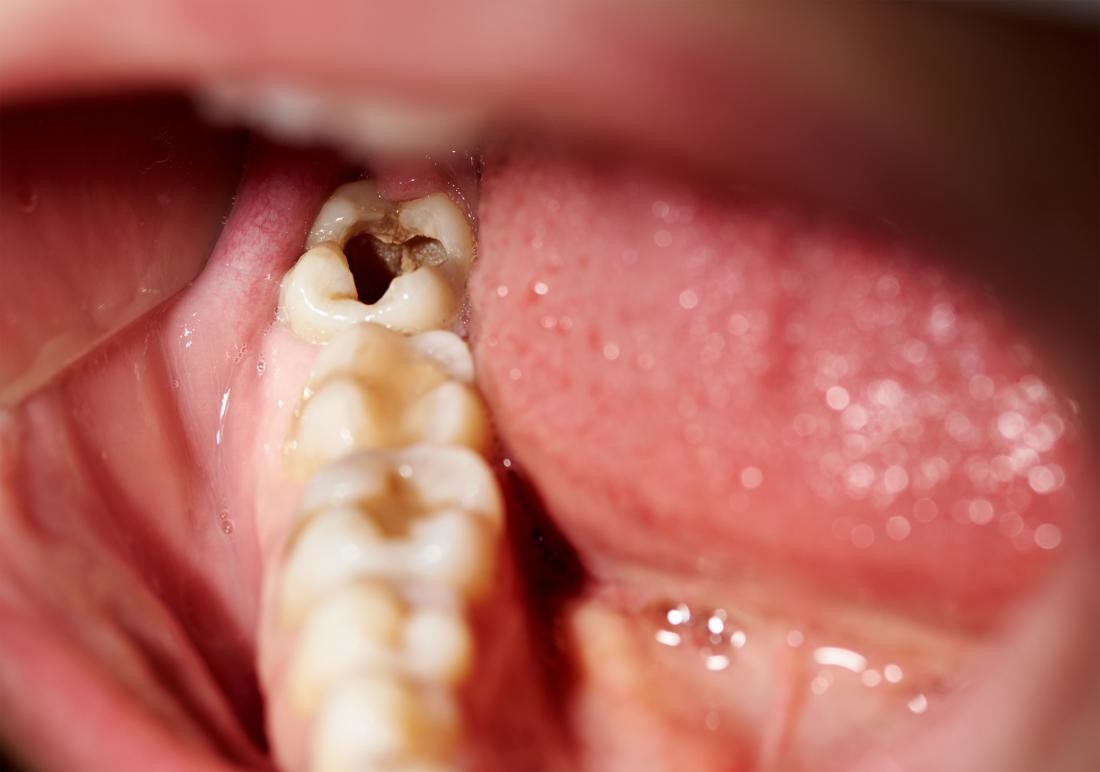

A rotten tooth is one that is severely decayed. The decay, also known as dental caries or a tooth cavity, begins with the breakdown of the tooth enamel. Plaque builds up and combines with bacteria to break down the enamel. Once the enamel has broken down, cavities develop. If you fail to treat your cavities, they will get worse. Dental caries is an open invitation to bacteria to further invade your teeth and beyond.

Dental caries does not discriminate. A tooth cavity can happen at any age. Baby bottle tooth decay is a breakdown of enamel caused by the sugar found in formula and extensive use of a baby bottle. The formula will pool around the teeth and combine with bacteria which accelerates breakdown in enamel. The condition is most common with a rotten back tooth or rotten bottom teeth. Thanks to a variety of available treatments, we can restore even those teeth you may believe to be permanently damaged.

Visually, you might first notice discoloration as the enamel deteriorates followed by tiny holes in your teeth. You will also see dark spots as the decay becomes more apparent. As the decay gets worse, the toothaches will become unbearable, your teeth can crack, pieces of your teeth can break off, or a tooth can completely break at the gum line. You will start having trouble eating and may lose weight. It is possible you will lose important nutrients that are critical to your health. The symptoms of a rotten tooth will grow more severe as time goes by. You are more likely to notice this kind of symptom in a rotten back tooth or rotten bottom teeth. In comparison, rotten front teeth are relatively rare.

There are three tooth decay stages. Early-stage decay is little more than an initial breakdown in the tooth enamel. There might be very tiny cavities, but early tooth decay stages can usually be reversed. Advanced tooth decay stages show significant cavities. At this stage, dental caries has gone further than just the enamel but have not yet reached the pulp of the tooth. Very advanced tooth decay stages show dental caries in the pulp of the tooth.

Decay that occurs on either your back teeth or your bottom teeth is treated with traditional fillings and crowns. It is more common for your back teeth to decay because they are harder to reach and may not get the care that your front teeth do when you brush and floss. No matter what stage of decay, you will notice a difference in your rotted teeth before and after treatment. With several options available, your rotten teeth do not need to be considered permanently damaged. The rotten teeth treatment options for each stage of decay are: